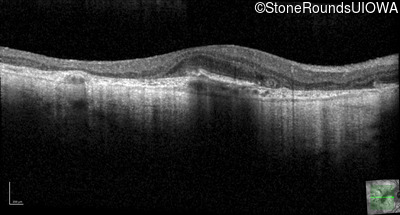

AR Stargardt Disease (IIA)

Age at visit: 51 years

This 51 year old woman first experienced some abnormality in her distance vision when she was 27 years old. She feels that her vision has been stable since that time.

Diagnosis & molecular findings

Disease Gene Allele 1 variant(s) Allele 2 variant(s) Inheritance mode

AR Stargardt Disease ABCA4 Gly1507Arg GGG>AGG IVS42+1 G>A AR